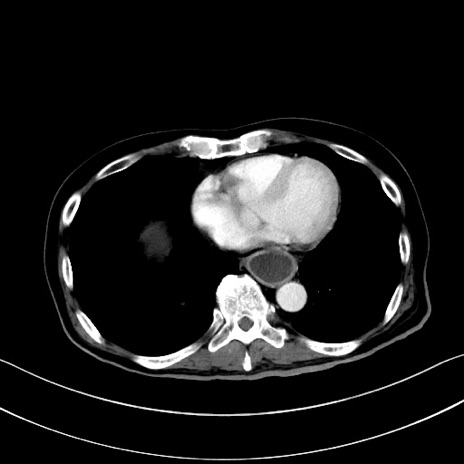

症例28(横断像)

【症例】60歳代男性

【現病歴】胃癌にて胃全摘後。食思不振が悪化し、夜中に嘔吐することがある。

【既往歴】胃癌、胃全摘、脾摘、胆摘後